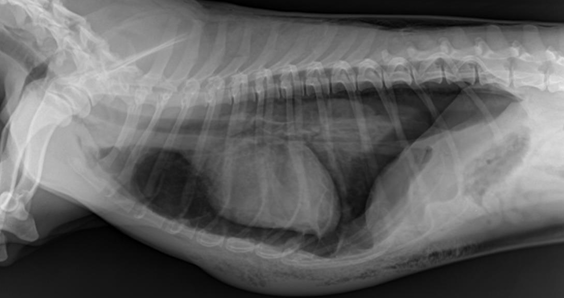

![]() | Megaesophagus - Mediastinum에서 만날 수 있는 변화 - 생각보다 흔함 - 거대식도+호흡기 증상 ⇒ 오연성 폐렴 동반. |

![]() | Mediastinum - abnormal shift - 여기서는 심장이 오른쪽으로 붙음 - 무기폐, 폐자름술, 폐종양일 때 발생 |